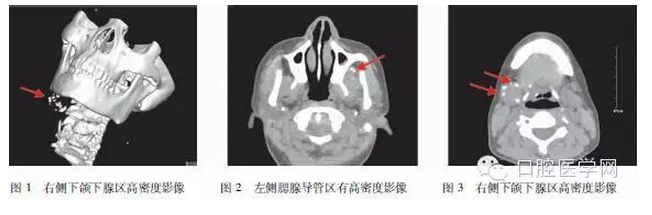

影像學(xué)檢查:CT影像(圖1~3)右側(cè)下頜下區(qū)可見大量散在分布高密度影,左側(cè)可見腮腺區(qū)亦有高密度影像。